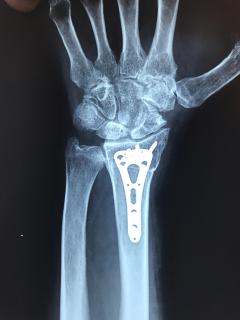

Kαρπός - Ασθενής 1 - Mετεγχειρητικά